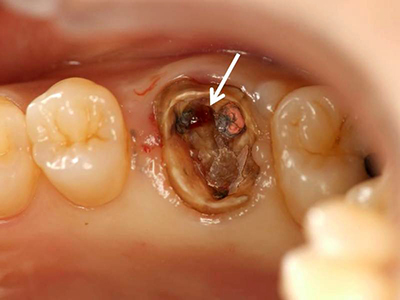

根尖病巣による典型的な歯茎の腫れ。不良根管治療や歯髄壊死では、根尖部(歯根の先端)の炎症によって生じた膿が体外に排出されるため、歯茎が腫脹します(矢印)。

歯根に誤って穴を開けてしまうケース(矢印)

歯根に誤って穴を開けてしまうパーフォレーション(矢印)、小さなものではMTAセメントでリペアできるものもあるが、大きなものや陳旧性のものは予後が悪く、抜歯の適応になる。